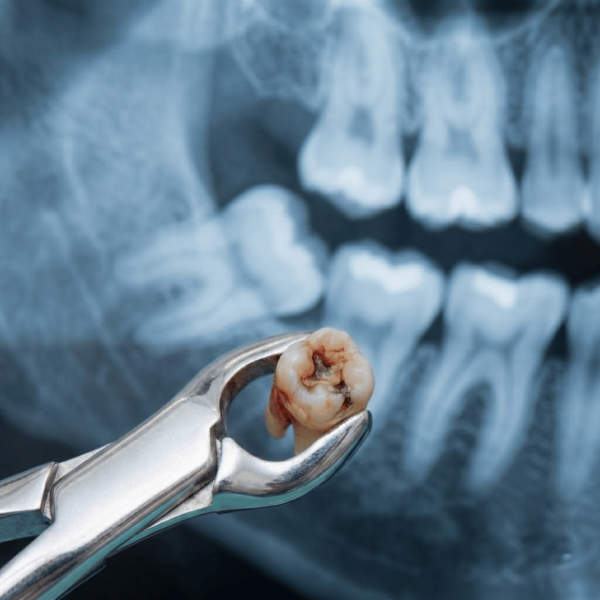

Wisdom teeth are the final set of molars that emerge at the back of the mouth. When these teeth cannot erupt normally or become stuck in the jawbone, they require surgical removal. This procedure is known as wisdom tooth extraction. It is a common yet sensitive dental procedure that should only be performed by specialist dentists to ensure safety and precision.

Are you suffering from unbearable wisdom tooth pain? Often, these teeth, which grow at the very end of the gums, do not find enough space to emerge properly. As a result, they grow at an angle or remain trapped within the gum—a condition known as an impacted wisdom tooth. This doesn’t just cause pain; it can damage your adjacent healthy teeth and overall jaw health. At Tech Dental, we provide a gentle, painless, and modern solution for your wisdom tooth troubles using advanced technology and expert surgical care.